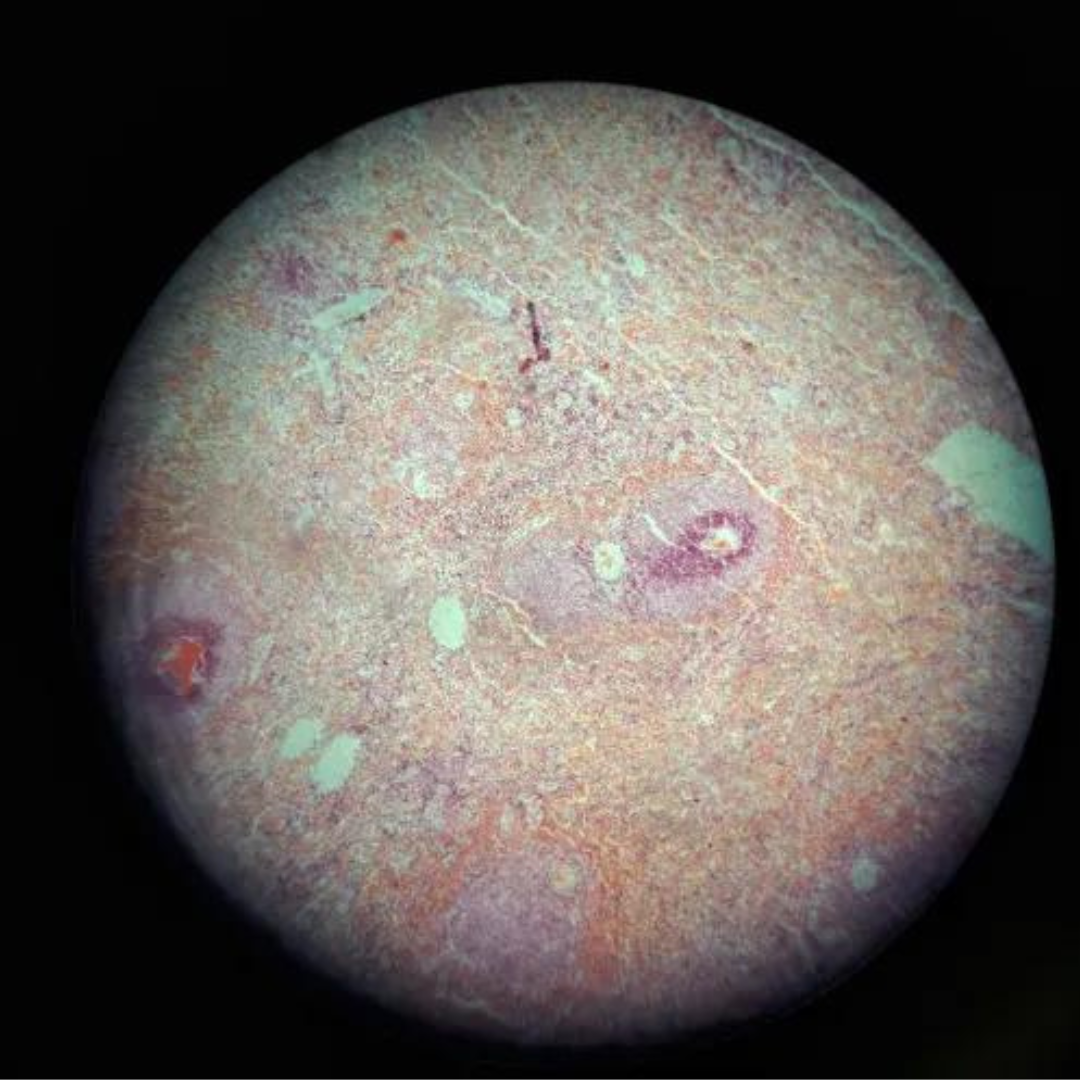

Spleen

21

New cards

Spleen

22

New cards

Spleen

23

New cards

Spleen

24

New cards

Spleen

25

New cards

Spleen

26

New cards

Spleen

27

New cards

Spleen